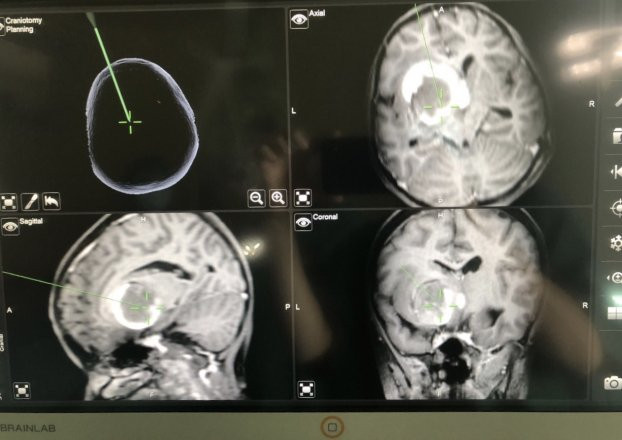

Hình ảnh khối u trong não trẻ có kích thước lớn, 6x7cm

TS.BS Nguyễn Đức Liên, Trưởng khoa Ngoại Thần kinh, Bệnh viện K cho biết, khối u của Nhi lớn, kích thước 6x7cm nằm ở vị trí trung tâm não, ảnh hưởng rất nhiều chức năng quan trọng, khối u gây ứ nước trong não.

Ngày 14/11, trẻ được mổ bóc tách khối u não. Ca mổ kéo dài 4 tiếng, các bác sĩ lấy được toàn bộ khối u mà không làm tổn thương đến các cấu trúc khác của não. Ca mổ được thực hiện dưới kính hiển vi có hệ thống dẫn đường đảm bảo độ chính xác cao nhằm không làm tổn thương đến các tổ chức khác của não.

Đường mở xương sọ nhỏ chỉ khoảng 4 cm. Việc mổ bóc toàn bộ khối u sẽ giúp trẻ khỏi bệnh hoàn toàn.

Ca mổ được thực hiện dưới kính hiển vi có hệ thống dẫn đường đảm bảo độ chính xác cao